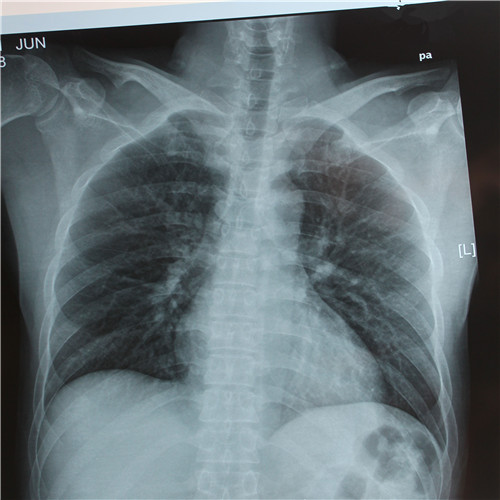

呼吸道感染胸片檢查